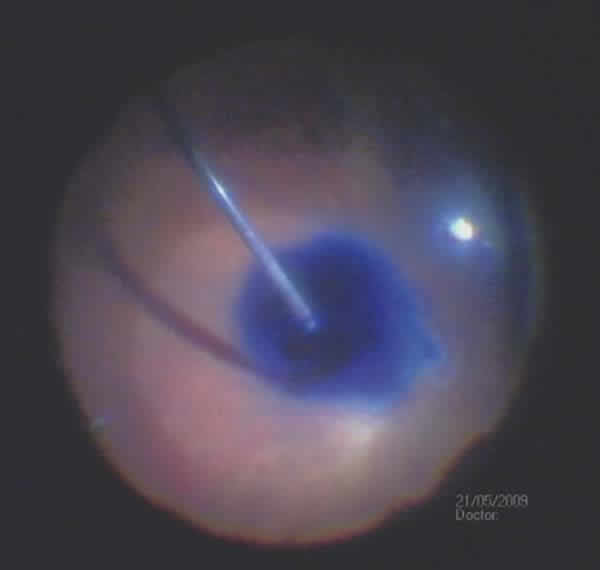

ICG is an anionic vital dye having the theoretical formula C43H47N2NaO6S2 (although it includes about 5% of iodine derived from the synthesis process), and a molecular weight of 775 daltons. It bonds both to cell elements (ERM, fig. 2) as non-cell elements (ILM). It is usually in lyophilized sterile form ready for dissolving in distilled water. In 1959 it was approved by the FDA as an indicator of bodily dissolutions and in liver function tests. ICG is utilized in angiography because it allows the study of choroidal circulation, with the absorption and fluorescence peaks being found in the near infrared spectrum.

Fig. 2: Staining and peeling of the epi-retinal membrane (ERM) after ICG injection.

Tests in pig models determined that, after exposure to light, ICG increases the biochemical rigidity of ILM, thus facilitating its peeling. A vast amount of papers have been published describing ILM peeling as less traumatic than peeling without staining, and with good clinical results, achieving between 74% and 100% of macular hole closures after peeling with ICG (figs. 3-4). In diabetic macular edema cases, the utilization of ICG in ILM peeling has been followed by visual improvements. However, in persistent macular edema after occlusion of the central retinal vein and Irvine-Gass syndrome, no significant clinical improvement has been observed.

Fig. 3: Internal Limiting membrane (ILM) staining and peeling in a macular hole case after ICG injection.